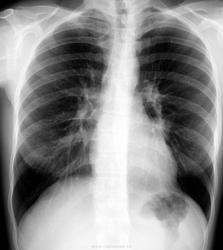

Молодой человек 30 лет. Проводил ц ФГ в 2010 году, после чего был направлен на дообследование (КТ). Сейчас пришел на контроль, протокол КТ предстваил лично.

От бокового снимка отказался...увы. Что скажете?

Шаровидная тень: в S4 в/доли слева (1 случай) и S10 н/доли справа (2 случай)

Татьяна Валентиновна, асолютно согласен. что основной рентгенологический признак - шаровидные тенеобразования, но...достаточно ли они "шаровидны" и достаточно ли однородны....+молодой, в общем то возраст, + отсутствие существенных жалоб. Конечно, смущает тот факт, что это не первые их ФГ (но у меня то они впервыеwink). Опять же - в С10 (скрывается за тенью печени), в С4 слева (не факт, что раньше было перекрыто левым краем сердца) и, как следствие - не были обнаружены.

Внутрилегочная секвестрация или артериовенозная мальформация.

..... артериовенозная мальформация.

Она самая))). Да, оба случая подтверждены на КТ.

Нечего сказать. Вспомнился мой же №5'). из вопросной ветки... С одной стороны патология видна и на обзорных (в обоих случаях). С другой - с учётом отсутствия жалоб, клиники диф. ряд получился бы немалым. Приоритет диагностики в отношении а/в мальформаций, конечно, у КТ/МСКТ, но гарантирую, что во втором случае с парнем поставил бы (если бы не забыл по такой Rg-картине) эту нозологию далеко не в первых числах...